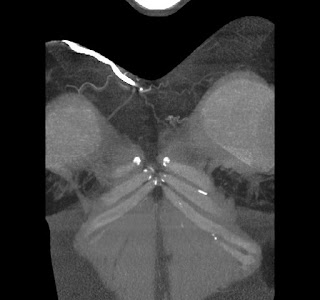

40 year old female. Breast implants 17 years ago, most likely Dow Corning. Symptoms from upper body for 6-7 years. Pain in breasts, ribs, back, neck. Skin rash. Headache and dizziness, weakness, numbness and vision disturbing. Sudden sleep episodes. Painful lymph-notes. These images are from 2010 and diagnose results were "No findings". Patient is scheduled for explantation in mid Feb. 2012